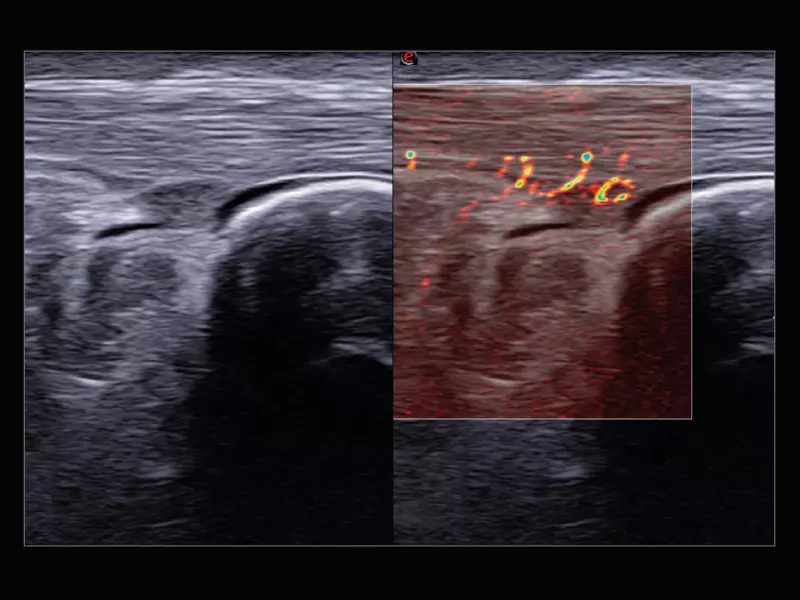

MyLab™9 Platform - Advanced hemodynamic analysis in thyroid nodule with microV

MyLab™9 Platform - Advanced hemodynamic analysis in thyroid nodule with microV